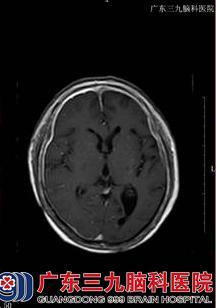

71岁的刘某本可在家安度晚年,坐享天伦之乐,可是,就在一年多前,她出现了右侧头部疼痛,阵发性枕部牵拉痛,持续数分钟至数小时不等,每天上午约11时出现剧烈疼痛,到相关医院进行眼眶CT示双侧眼球内斜位,头颅MRI+MRA示右侧额叶、基底多发性腔梗,右侧中后组筛窦、蝶窦,暂考虑炎症,由于刘某还出现了视力下降,在眼科医院眼球彩超室双侧玻璃体混浊(+)伴后脱位。脑脊液常规示白细胞17*106/L,脑脊液生化示蛋白0.87g/L,颅脑MR增强示双侧大脑及小脑幕脑膜增厚,右侧明显,考虑一个脑膜炎,给予相关治疗后,效果差,2014年10月,刘某左眼亦出现视力下降,到其他医院行头颅MRI+增强示弥漫性硬脑膜强化并右额颞部硬膜下小血肿,脑脊液常规示白细胞20*106/L,脑脊液生化示蛋白1.714g/L,再接受相关治疗后,刘某仍感不适,遂到广东三九脑科医院进一步治疗。

收治入院后,完善相关检查发现:患者意识清楚,懒言少语,言语不清,记忆力、计算力、定向力等认知功能下降,MMSE13分(存在认知功能障碍),右侧眼裂小,右眼失明,右侧瞳孔扩大,直接对光反射迟钝;左侧瞳孔正常,直接对光反射稍迟钝,余脑神经(-),双下肢肌力五级弱,肌张力正常,双侧腱反射(++),左侧Babinski征、Chaddock征均(+),颈部绵软,Kernig征、Brudzinski征均(-),双侧指鼻试验、快复轮替动作及跟膝胫试验均完成。故初步诊断为:1、头痛查因:硬脑膜炎(特发性肥厚性)?2、脑梗死?3、硬膜下血肿(恢复期)?神经内二科王展航主任在详细了解病人病情后,制定了详细的治疗方案,给予病人改善脑循环、神经营养、激素、康复治疗等加强对症支持治疗。

【头颅MRI结果】: